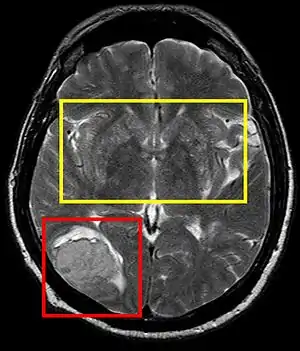

Stroke brain (similar to cerebral softening)